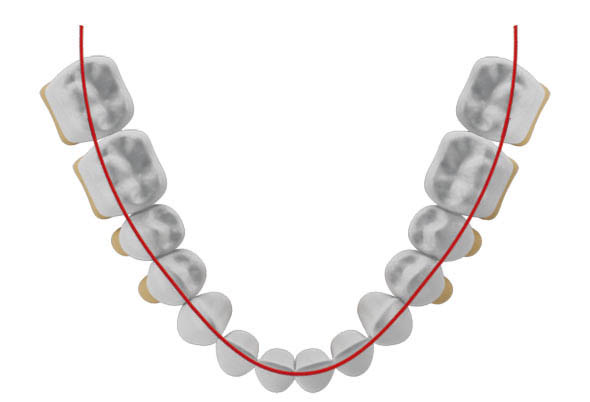

شکل 27-2: دندانهای بیمار درون قوس هستند خط قرمز قوس فکی را نشان میدهد.

شکل 28-2: وقتی انسیزورها پروترود شوند باکالیتر از خط قرمز که نشاندهنده قوس فکی تصویر قبلی است قرار میگیرد.

درشکل 40-2 قوس فکی را مشاهده میکنید.